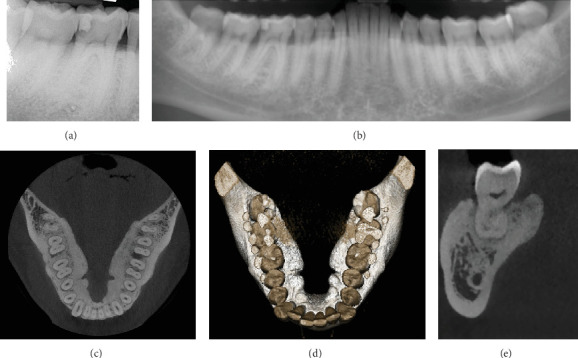

Background: Oral exostoses, including mandibular tori, are benign bony outgrowths that can lead to functional impairments when large. Spontaneous exposure of a mandibular torus is a rare event that requires surgical intervention. Case Presentation: A 33-year-old male presented with bilateral mandibular tori. The right mandibular torus had spontaneously exposed, causing pain during mastication, swallowing, and phonation. Surgical removal of the exposed torus and extraction of a carious tooth were performed under local anaesthesia. Conclusion: The patient recovered without complications, and no recurrence of symptoms was noted during the 1-year follow-up. This case highlights the need for prompt surgical intervention in cases of spontaneous torus exposure and the importance of histological analysis.